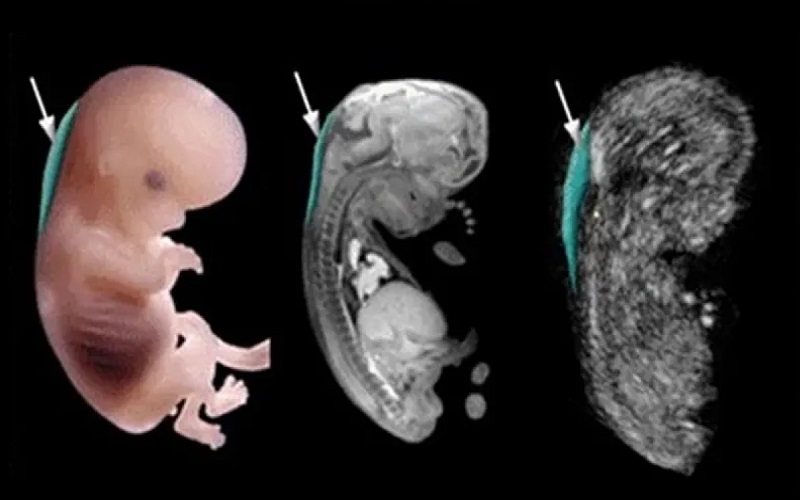

سونوگرافی NT

نوعی سونوگرافی پیشرفته است که برای اندازه گیری میزان ضخامت مایع پشت گردن کودک کاربرد دارد. مایع پشت گردن نوزادان مبتلا به سندروم داون از حالت طبیعی بزرگتر است. بهترین زمان برای انجام سونوگرافی nt حد فاصل هفته ۱۱ تا ۱۳ بارداری میباشد.

سونوگرافی آنومالی

در اصطلاح به این نوع سونوگرافی آنومالی، غربالگری آناتومی جنین نیز گفته میشود که در آن تمامی اعضای حیاتی بدن مانند قلب، کلیه، مغز، معده، کبد، مثانه و سایر اعضا نیز مورد بررسی قرار میگیرند. اندازه سر جنین و شکل آن گویای موارد طبیعی یا غیر طبیعی در جنین میباشد البته ناگفته نماند که احتمال وجود ناهنجاری های مغزی نسبت به سایر بیماری ها پایین تر است.